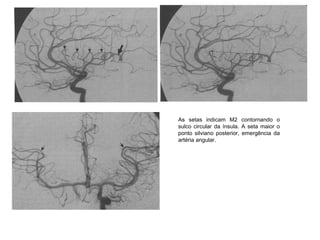

As setas indicam M2 contornando o

sulco circular da ínsula. A seta maior o

ponto silviano posterior, emergência da

artéria angular.

As setas indicamM2 contornando o sulco circular da ínsula. A seta maior o ponto silviano posterior, emergência da artéria angular.